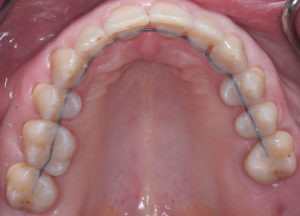

Для предварительной подготовки были привлечены пародонтолог и ортопед, поскольку отсутствие нескольких зубов, заболевание пародонта и дефекты твердых тканей зубов сопутствовали основной патологии. Проведены пародонтологические процедуры, вылечен кариес и его осложнения, изготовлены временные коронки для зубов с большим разрушением. На фото — временные коронки на боковых зубах.